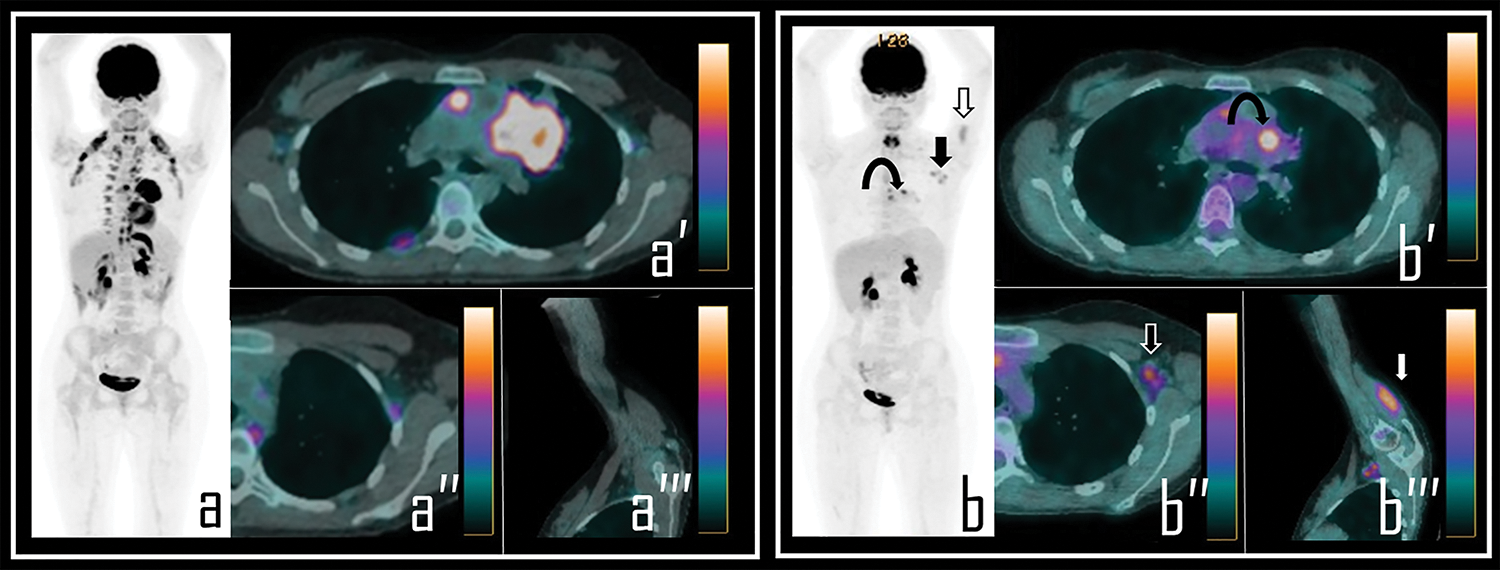

We observed axillary and/or deltoid 2-[18F]FDG uptake, related to COVID-19 vaccine administration, in 89/104 subjects (85%). Among these, 57/89 (64%) had received the first dose of vaccine prior to the PET/CT scan (Fig. 1) while 32/89 (36%) were also administered with the second dose (Fig. 2) of mRNA vaccine (see Table 2).

Figure 1: A 36-year-old male patient examined by 2-[18F]FDG PET/CT during the staging of Hodgkin’s lymphoma. Baseline PET/CT (a) showed a mediastinal bulky lymphoma, more evident in axial PET/CT view (a′). No abnormal foci of uptake were observed in left axilla neither in ipsilateral deltoid muscle, as showed in axial PET/CT detail (a′′) and oblique PET/CT view of the left arm (a′′′).

Note: After 2 cycles of chemotherapy, the patient underwent interim 2-[18F]FDG PET/CT, showing incomplete response to therapy in the mediastinal mass with residual lymphoid active tissue, as evident in PET Maximum Intensity Projection (b, curved arrow). PET also showed focal uptake in the left deltoid (b, white arrow) and in three ipsilateral axillary lymph nodes (b, black arrow). Residual lymphoma is evident in axial PET/CT view (b′, curved arrow) while axial PET/CT detail shows a 2-[18F]FDG-avid lymph node in left axilla (b″, black arrow), with SUVmax 2.5; oblique PET/CT view of the left arm displays diffuse uptake in the deltoid muscle (b′′′, white arrow), with SUVmax 2.8. The Patient underwent first dose of COVID-19 vaccine 9 days before the second PET/CT scan.